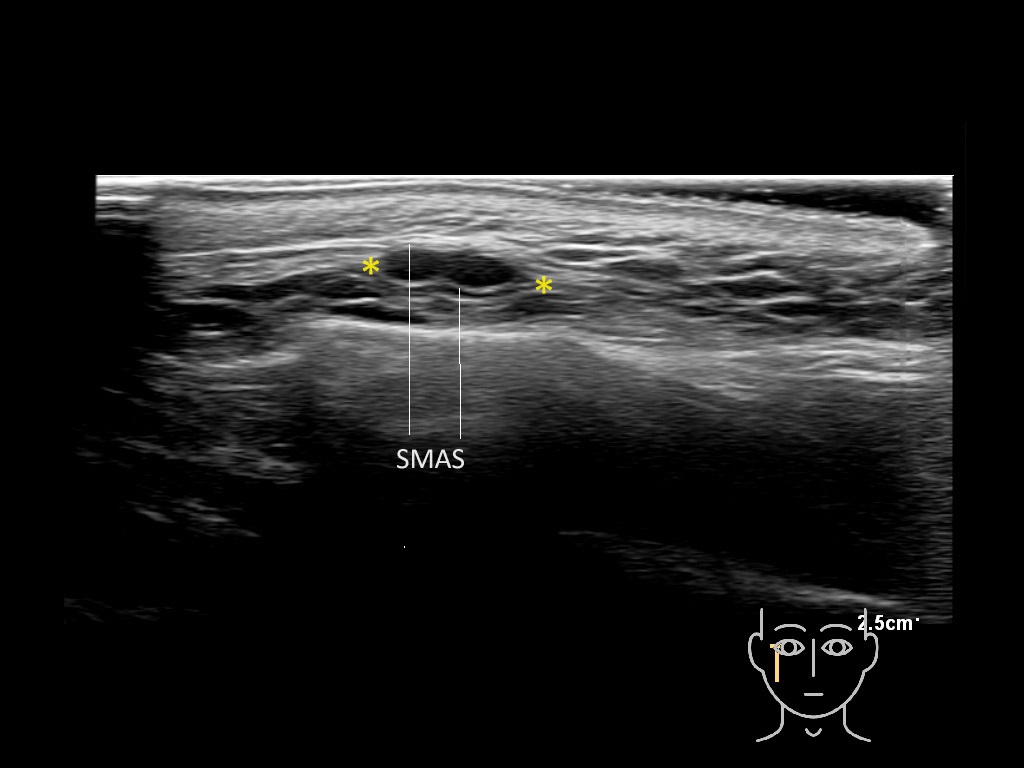

Filler deposits may end up unintentionally in the SMAS or fascial layers of the skin. Very often this will not lead to adverse events, however, adverse events ( nodules, migration / redistribution impaired muscle movement and smiling and malar edema) are are often related to filler ending up in the SMAS or fascia.

Study the first image to recognize the different layers. If you are sure about the layers, swipe to the second image to view the answer (if applicable).